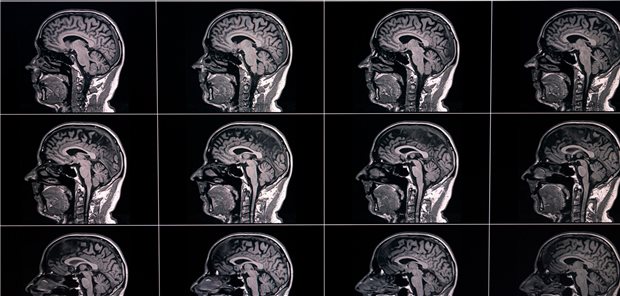

Größere Schmerzen in der frühen Kindheit scheinen mit einer Hypokonnektivität im neonatalen Gehirn verbunden zu sein, wobei die stärksten Assoziationen in den Basalganglien und den limbischen Strukturen beobachtet wurden. Eine verringerte strukturelle Konnektivität des Gehirns wurde mit schlechteren neurologischen Entwicklungsergebnissen nach 18 Monaten in Verbindung gebracht.

Sehr kleine Frühgeborene

Schmerzen beeinträchtigen die Hirnreifung – besonders bei Mädchen